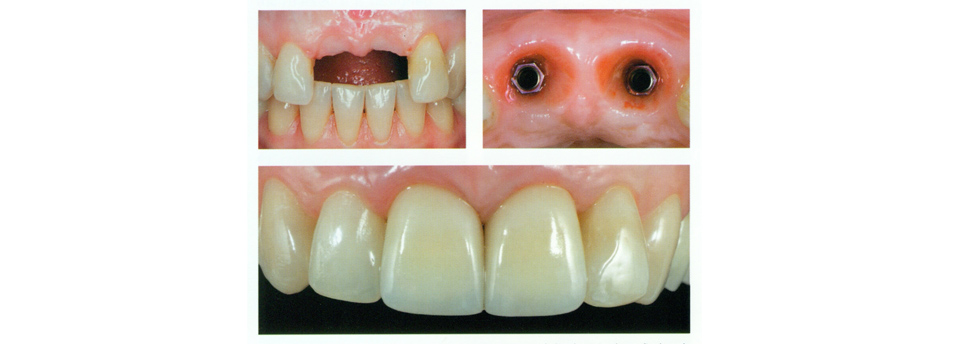

Missing teeth can be a nuisance, both cosmetically and functionally; you may feel self-conscious about a gap in your smile, and that gap will almost certainly cause problems with biting and chewing. While there are several procedures dentists use to fill in gaps left by missing teeth, dental implants are by far the most natural-seeming in form and function. A dental implant is nearly indistinguishable from a natural tooth and can last a lifetime with proper maintenance. Click here to find out more.